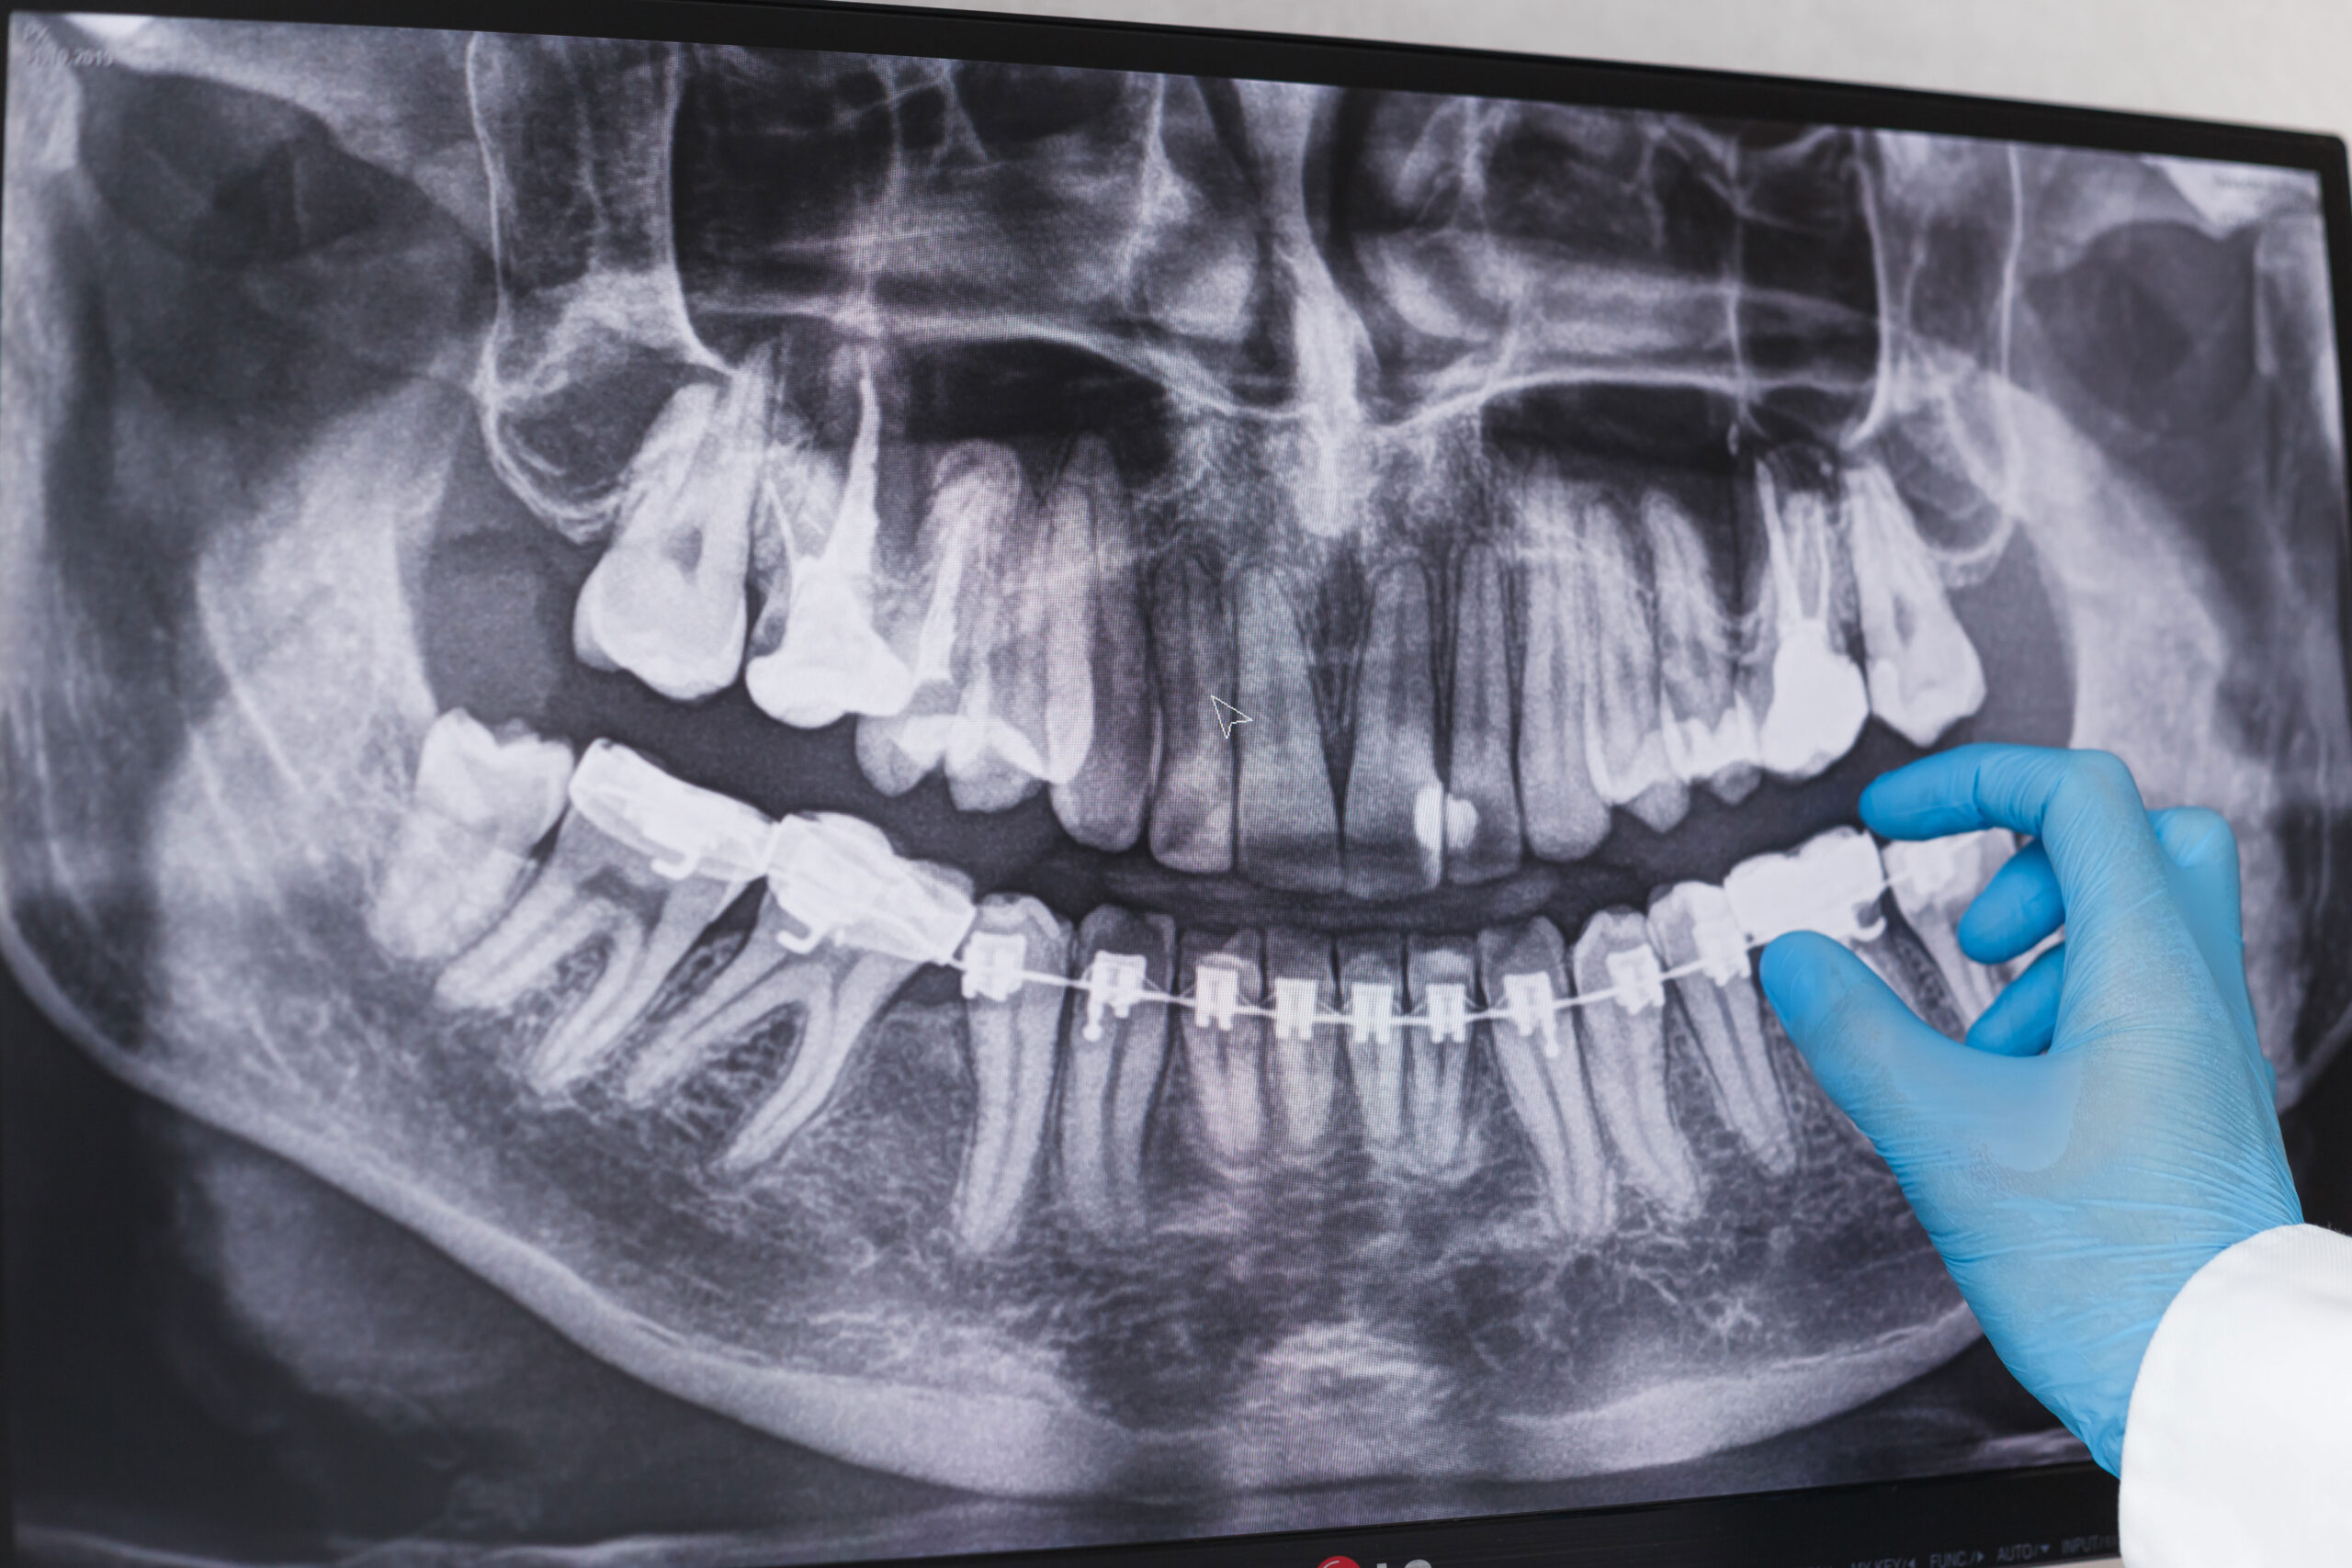

La dottoressa Amy Hartsfield, specialista in dolori orofacciali e medicina dentale del sonno dell’Alabama, ha dichiarato alla testata americana Epoch Times di aver visto un massiccio aumento di pazienti con disturbi gravi tra coloro che hanno fatto il vaccino COVID.

«Da quando i vaccini sono stati lanciati, Hartsfield ha visto un aumento esponenziale di pazienti con dolore neurovascolare e miofasciale alla testa e al viso, inclusi mal di testa, mal di denti non causato dal dente, osteonecrosi della mascella, problemi di sonno, tinnito e condizioni autoimmuni orali e facciali» scrive il giornale statunitense.

«Ho visto pazienti senza precedenti di problemi di salute che hanno denti perfettamente sani e ora hanno sindromi dolorose associate a questi denti sani», ha detto. Questi tipi di lesioni, sostiene l’odontoiatra, colpiscono sia i nervi che i vasi sanguigni.

La dottoressa Hartsfield afferma di aver scoperto una miriade di problemi di salute causati dalla proteina spike del vaccino COVID e dalla sua tendenza a causare «micro» coaguli di sangue.

Viene quindi raccontato il caso di Cheryl Alverson, che ha iniziato a sperimentare una grave perdita ossea dopo il vaccino mRNA. «Cheryl Alverson, 79 anni, è arrivata a Hartsfield dopo essersi fatta estrarre tutti i denti inferiori a causa di una massiccia infezione ricorrente che ha causato un’estesa perdita ossea. La Hartsfield ordinò immediatamente più esami del sangue, inclusi molti specificamente correlati alla coagulazione del sangue. “Hanno mostrato che avevo microcoaguli in tutto il corpo”, ha detto Alverson».

Hartsfield ha spiegato che i microcoaguli possono interferire con la guarigione ossea dopo le estrazioni. Quello che è successo con la Alverson in genere si verifica solo in pazienti che hanno assunto farmaci per l’osteoporosi o hanno subito radioterapia, nessuna delle quali si applicava ad Alverson. La paziente aveva fatto i vaccini Moderna COVID-19 e una successiva dose di richiamo prima che iniziassero i suoi problemi, e non era stata infettata dal virus COVID-19.